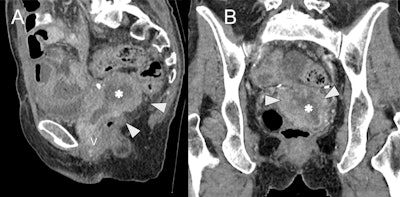

OHVIRA syndrome. (A) Sagittal ultrasound image at the level of the uterus (U) shows echogenic contents distending the vagina (asterisk) with (B) no color Doppler flow. (C) Axial T2w MRI shows two widely splayed uterine horns (white arrowheads). (D) Coronal T2w MRI demonstrates two separate cervices (white arrowheads) and vaginal cavities (black arrowheads) consistent with uterine didelphys. The right hemivagina is distended with fluid (asterisk), consistent with obstruction. (E) Coronal fat-suppressed T1w MRI at the same level shows low signal intensity of the vaginal contents (asterisk), suggestive of hydrocolpos. (F) Wide field-of-view fat-suppressed T2w MRI shows right renal agenesis (dashed line) ipsilateral to the side of vaginal obstruction (asterisk). All figures courtesy of Dr. Monish Ahluwalia, Dr. Andrew Chung, and EJR.

“Transabdominal and transvaginal ultrasound is the first-line imaging modality, which demonstrates uterine didelphys, echogenic hematocolpos or hematometrocolpos, and unilateral renal agenesis. There should be no colour Doppler flow in the vaginal contents to differentiate from a vascular mass. Care should be taken to appropriately delineate anatomic structures, as hematocolpos can be mistaken for a pelvic abscess or endometrioma,” the authors pointed out.

MRI allows for detailed delineation of uterine morphology and the continuity of each vaginal channel, in addition to the findings on ultrasound. Low signal on T1-weighted imaging (T1-WI) suggests hydrocolpos, while high signal indicates blood contents. CT may show similar findings, albeit with lower contrast resolution.